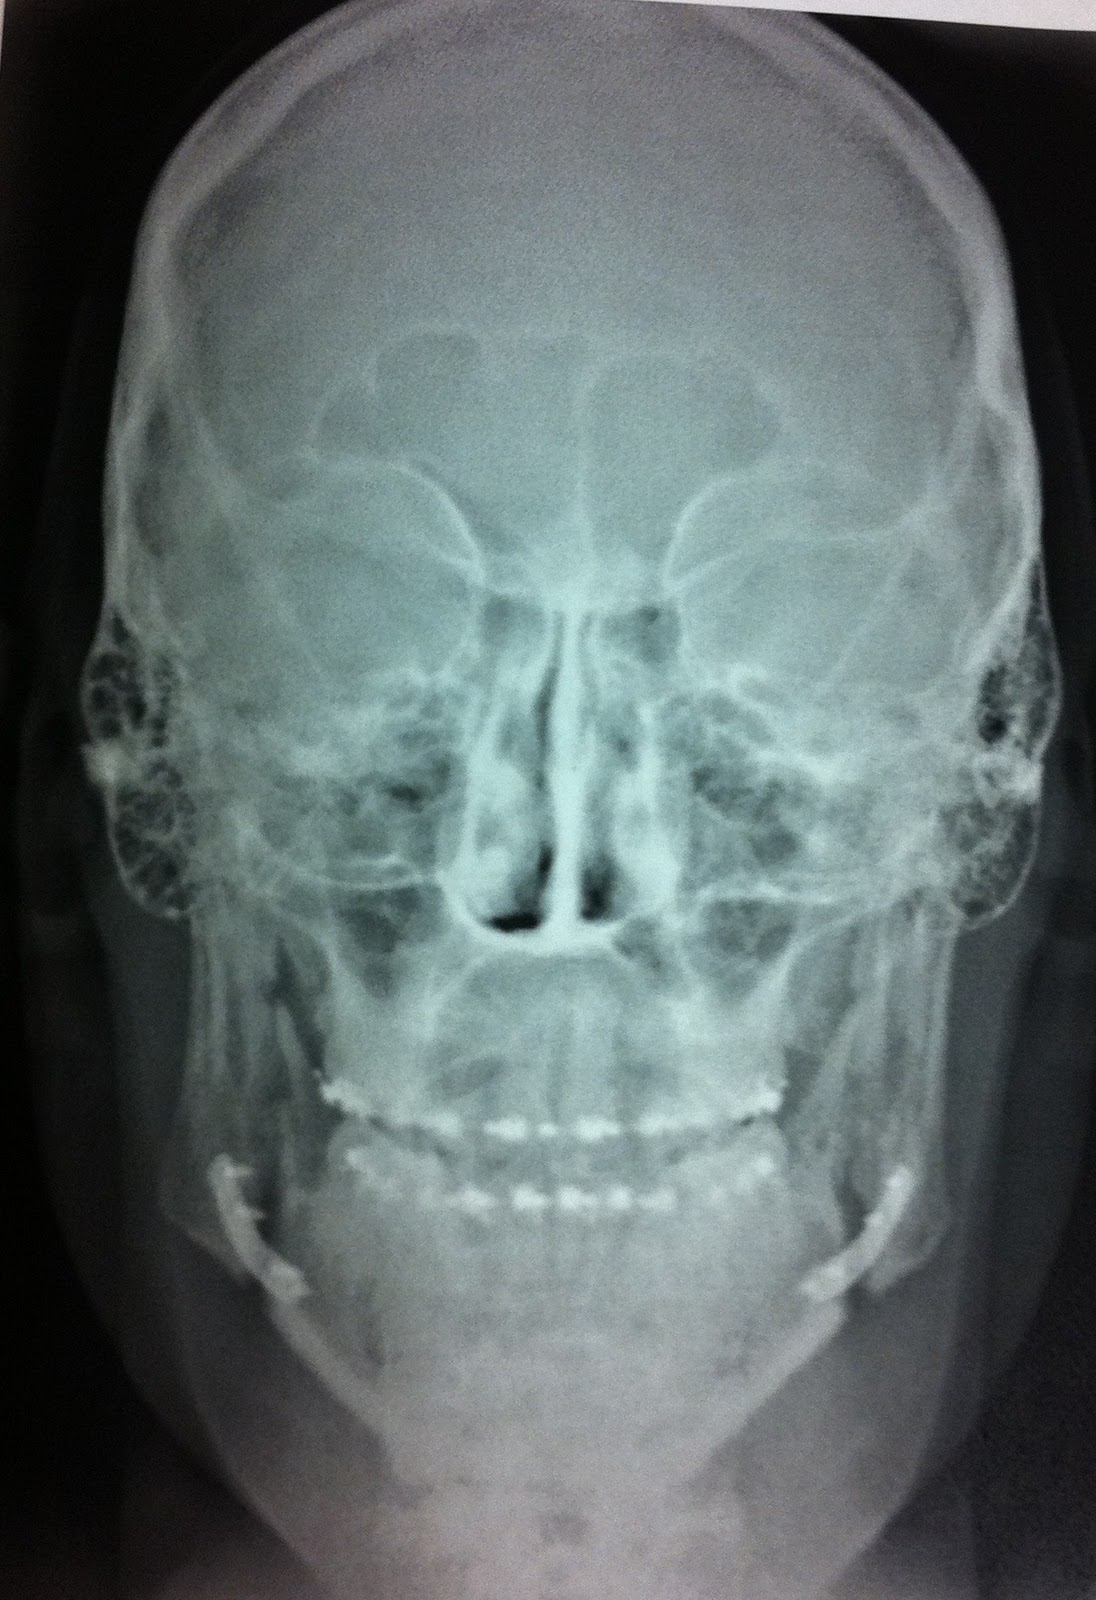

Friday morning, (day 5) I had my follow up with Dr. T.  It went really well, got some really cool X-rays and got some really good news and some really not-so-good news.

He was really happy with the way things turned out. Said I was a perfect patient!  Well not really, I threw that part in there, but he did say that things went perfectly.  He was REALLY pleased with how everything lined up and with the fact that I have very little-to-no numbness at all.

I asked why I didn't have incisions and stitches on my cheeks as expected, and he said, "Well that's why your lips were so split."  He said he was able to get my mouth open enough to be able to do everything he needed to do from the inside. Which was awesome!  He also said that the final measurement was about a full CM forward. 9-10mm!  Last I heard from Dr. Simon we were looking at about 6.  WOW!  That's a big jump!